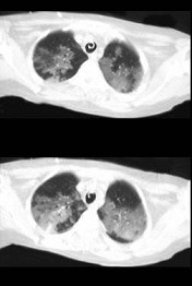

男,32岁,干咳,呼吸困难半月余,2月前被诊断为艾滋病,结合影像学检查,最可能的诊断是( )

A:肺结核

B:卡氏肺囊虫性肺炎

C:肺癌

D:大叶性肺炎

E:间质性肺炎